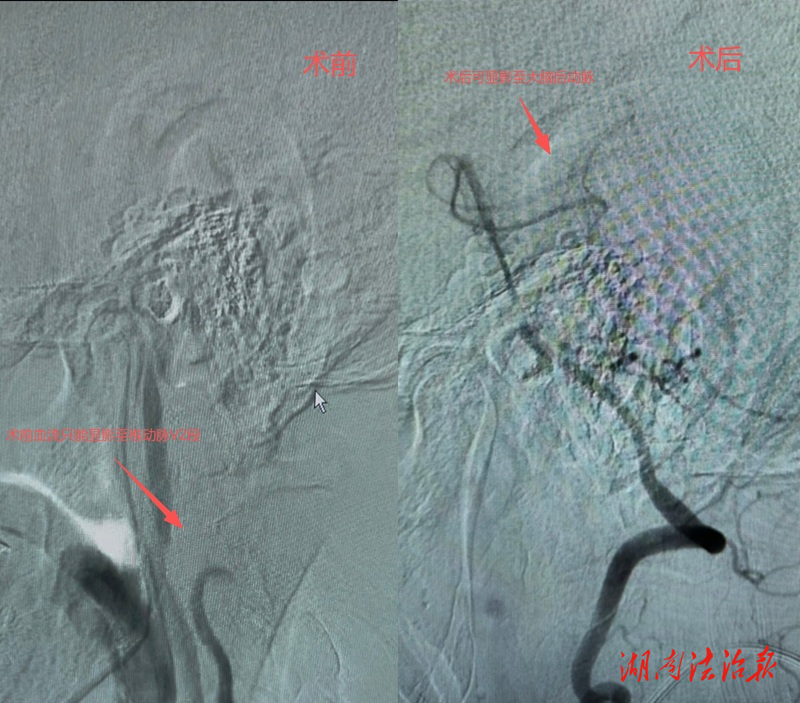

本次手术患者为74岁男性,因脑梗死入住该院中风科。入院后,科室团队详细问诊查体、完善各项检查,经数字减影血管造影(DSA)确诊:右侧锁骨下动脉起始部重度狭窄,狭窄程度超 90%,合并锁骨下动脉盗血综合征。该病症若延误治疗,极易诱发再次脑梗死、上肢缺血性坏死,严重危及生命,具备明确手术指征。

手术过程精准顺畅,介入团队娴熟运用球囊穿梭、特洛伊木马等先进介入技术,顺利完成股动脉穿刺、导丝导管通行、球囊预扩张、支架精准输送定位与释放全部操作。术中实时造影显示,患者狭窄血管完全开通,支架位置精准、血管壁贴合良好,脑部及上肢血流恢复通畅,盗血现象即刻消除,双侧上肢血压恢复对称,手术全程顺利完成。